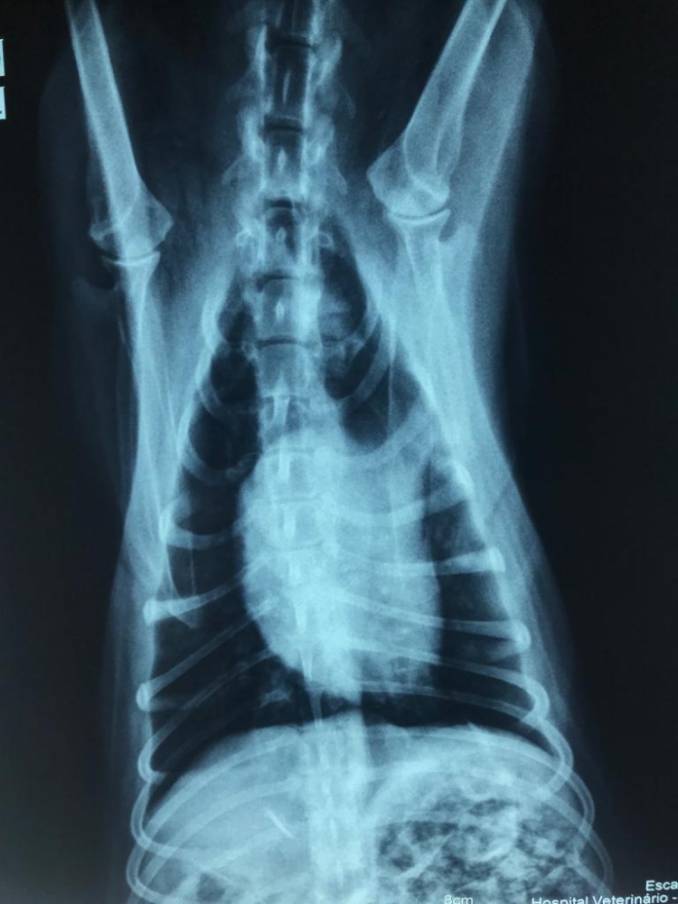

O Hospital Veterinário da Unijuí passou a contar, a partir deste mês de junho, com serviço de raio-X digitalizado. A tecnologia fornece imagem com melhor nitidez e definição, tornando a avaliação radiológica mais precisa, primando pela qualidade dos serviços.

Segundo a médica veterinária e professora, Gabriele Maria Callegaro Serafini, a radiografia digitalizada em tela de computador permite mais agilidade no atendimento. Quem realiza as radiografias é o técnico de radiologia, que passou por treinamento para o uso do equipamento. Além disso, os estudantes do curso de Medicina Veterinária ganharam mais um instrumento para estudos. “A grande vantagem é que, na disciplina de Diagnóstico por Imagem, eles poderão ter acesso a essas radiografias, qualificando o aprendizado”, observa.